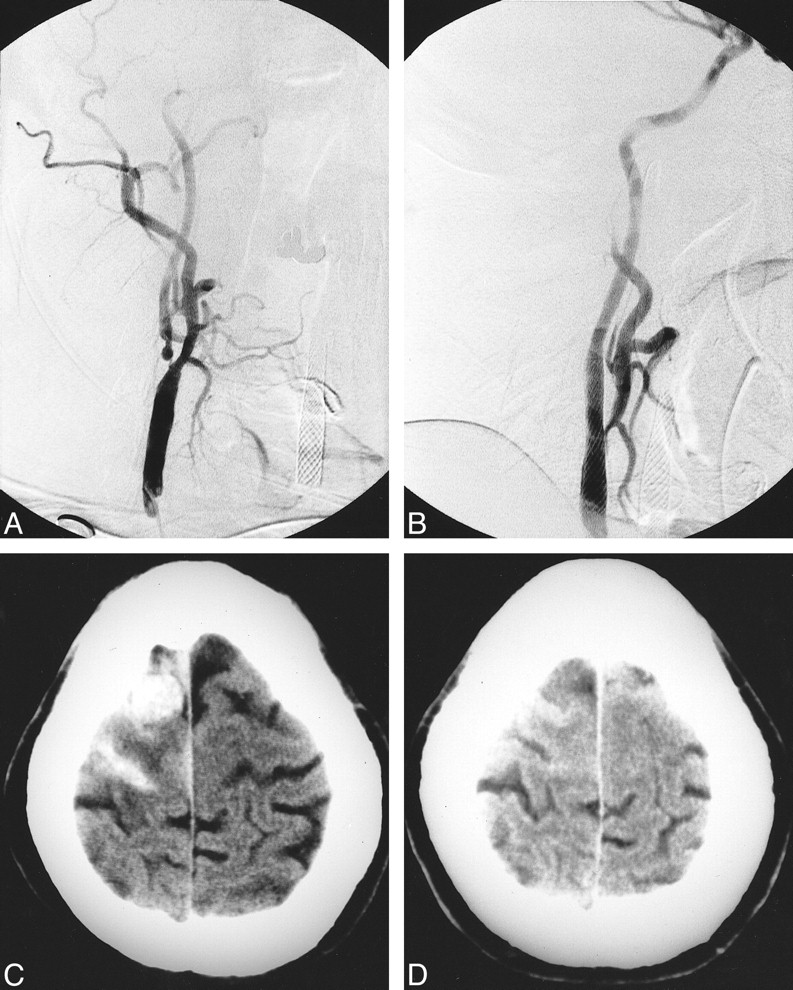

Patient 2. A, Ninety percent right internal carotid artery stenosis.

B, Postoperative angiogram shows a 30% residual stenosis post stenting.

C, CT of head at discharge shows an old, right, parietal infarct.

D, CT head 2 days postoperatively depicts a large, right, frontal hematoma with a small subdural hematoma.